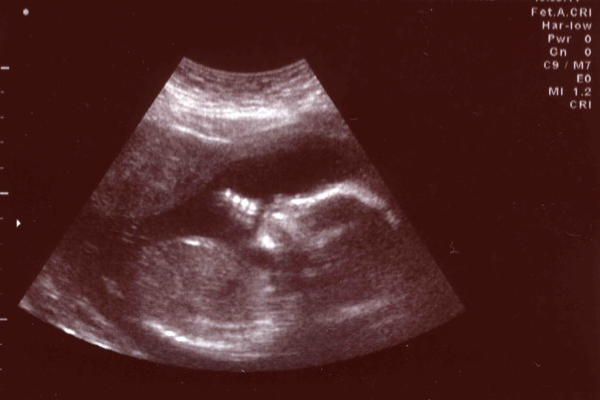

Tina* was 34 weeks pregnant and came in for a routine scheduled prenatal visit. “I haven’t felt my baby move in 2 days,” she said, “And he’s been moving less this past week.” She was a baseline anxious first-time mom. Every visit she asked lots of questions and was always worried if her baby was OK. Fetal heart tones were reassuringly 150s on the doppler.

It was Friday afternoon and I was seeing my last few patients before the weekend. As I was about to send her off I thought, “Let me just put her on the NST [fetal monitor recording].” Tina had gestational diabetes that was well-controlled by diet and the Maternal Fetal Medicine doctors stated she didn’t need extra fetal monitoring. They recommended it only for higher risk diabetics and it didn’t typically start until 36 weeks. But I just decided to do one anyway. After a few minutes on the monitor, I saw the heart tones appeared flat and with a small deceleration. I sent her immediately for monitoring at the Birth Center.

When the nurses hooked her up to the monitor, the fetal heart tones were not ominous but not completely reassuring either. I called the Maternal Fetal Medicine consultant and she reviewed the strip. “She’s a diabetic so we won’t give her steroids. So just go ahead and deliver her,” she told me over the phone. I was surprised. That wasn’t what I expected. She was 6 weeks from her due date and It wasn’t the worst fetal heart tracing I’d seen. I thought they would tell me to admit and keep monitoring her. If she had not been diabetic, we would’ve probably given her a course of steroids and waited.

As I pulled the baby out and placed him onto the drapes I was shocked. He was ghostly pale and there were two tight loops of umbilical cord lassoed around each thigh as if he had jumped into them and then they had been pulled tightly on both ends. He was limp and not breathing. Neonatology asked for the infant right away, rather than the usual delay for cord clamping.